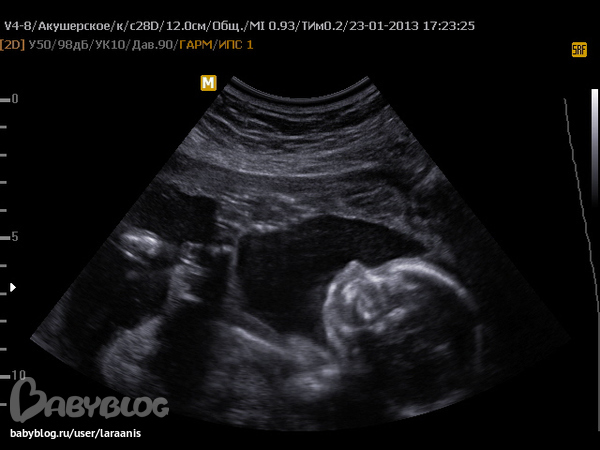

УЗИ в 20-21 неделю.

Вопросы про УЗИ, обследования и анализы: что, где, как, когда?Сходили с мужем на второе УЗИ. Красотааааа! У нас девчонка! Мы не поверили своему счастью! Хоть и готовили два имени - для обоих полов - надеялись тихо на дочь. И нам повезло!

Зато мы любуемся видео и фото, записанными на УЗИ. Наша Агата, кстати, 290 грамм уже весит))))))))))) только фотки что-то не грузятся...

такая сладенькая))а мне мою не показали в 20 недель((только в 12 фото есть,но там еще совсем зародыш,а тут такая ляля уже))